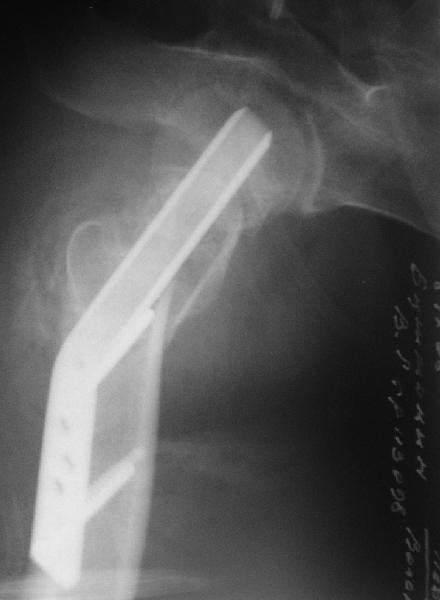

Re: Нелеченный перелом шейки бедра

Приветствую всех. Спасибо за активное участие в обсуждении. Выбрали вариант с остеотомией.

Снимки в приложении.